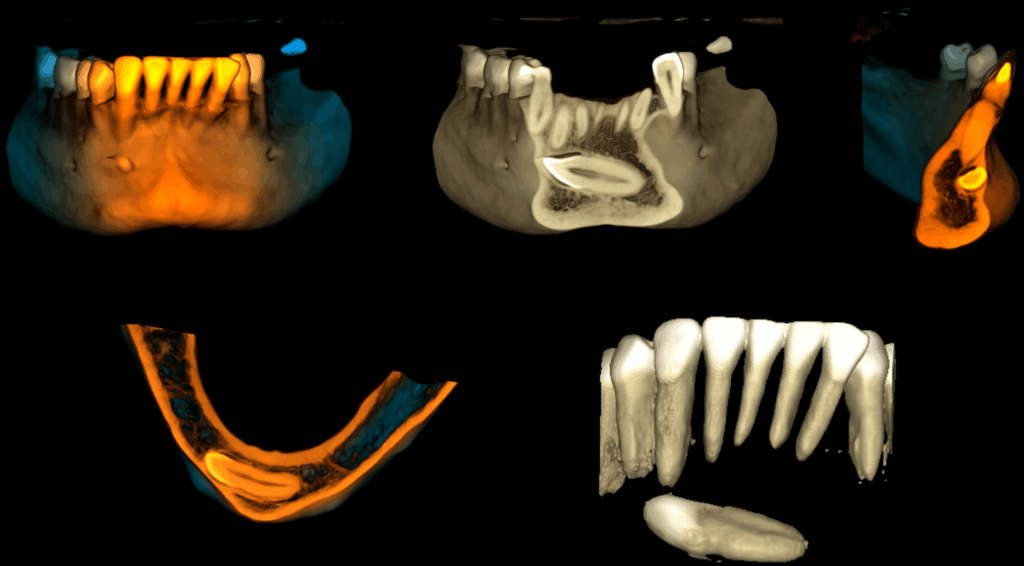

A la evaluación de la tomografía cone beam de campo mediano se puede observar que dicha pieza se encuentra caudal al ápice de las piezas 32, 31, 41, 42 y 43 con la porción coronaria en contacto y adelgazando la tabla ósea vestibular y la porción radicular se encuentra equidistante a ambas tablas óseas y la presencia de un foramen lingual. Se descartar cualquier relación con piezas dentarias vecinas

RECONSTRUCCIÓN 3D